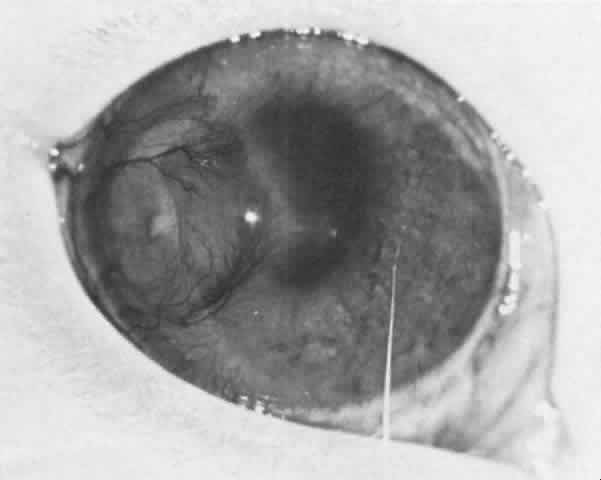

Both sympathetic ophthalmia and Vogt-Koyanagi-Harada disease (Fig. 8) are thought to be delayed hypersensitivities to melanin-containing structures.

Fig. 8. A young boy with Vogt-Koyanagi-Harada disease. The pigment alteration of the skin and the cataract OS secondary to the uveitis can be noted.END